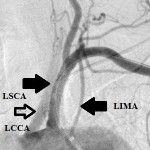

The 4 images you see above were recorded by me during primary stenting of irregular atherosclerotic stenosis of the left subclavian artery in a 54-year-old hispanic female who was referred to my interventional radiology clinic for management of the stenosis. She had presented to her primary care physician with symptoms of hindbrain ischemia upon using her left upper limb and earlier workup confirmed left subclavian arterial stenosis. The 2 top images illustrate the character and severity of her disease, the first image in the bottom row shows the process of balloon-expandable stenting of the disease, while the 2nd image in the bottom row reveals complete elimination of the stenosis and reappearance of the left vertebral and internal mammary arteires, which were invisible on the pre-intervention angiograms reflecting the severity of the stenosis.